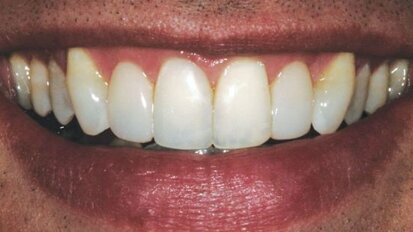

Rendre des facettes unitaires si naturelles qu'elles soient indétectables

Comme les patients vieillissent, les dents antérieures présentent souvent de l'usure, de l'effritement et de la décoloration. Ces ...

Planification prothétique rapide et facile

La plainte principale et la plus importante de cette jeune femme de 17 ans était le manque d'esthétique. Elle s'est également plainte ...